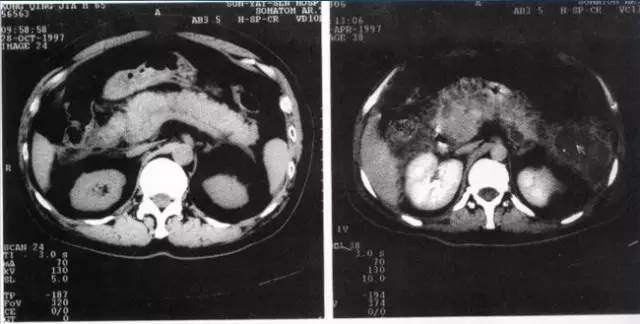

临床借助增强CT以明确急性胰腺炎的诊断并评估炎症反应及坏死程度,甚至也可以参考腹部B超及腹腔穿刺来帮助明确诊断。

(3)腹部影像学检查符合AP影像学改变。